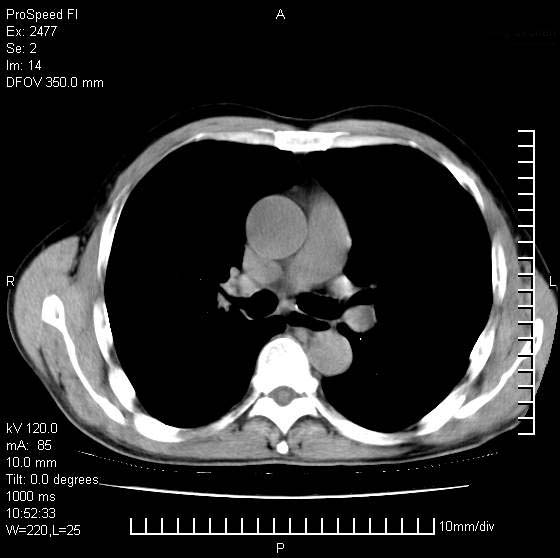

以下是引用天南地北在2007-10-9 14:29:00的发言:[br]1:右上肺结核[br]2:右肺下叶肿块:不支持肺癌,首先考虑炎性病变-肺脓疡可能性大[br]理由:1:临床病史支持,肺脓肿症状不明显应该是不规则服药造成。[br] 2:肿块边缘模糊,周围可见炎性渗出,长毛刺,内见支气管征,不过有点不规则。[br] 我感觉下肺癌这个诊断有点偏左,建议积极抗炎治疗后复查

以下是引用卜一在2007-10-9 15:55:00的发言:[br][br] [br] 1:右上肺结核[br]2:右肺下叶肿块:不支持肺癌,首先考虑炎性病变-肺脓疡可能性大[br]理由:1:临床病史支持,肺脓肿症状不明显应该是不规则服药造成。[br] 2:肿块边缘模糊,周围可见炎性渗出,长毛刺,内见空气支气管征,不过有点不规则。[br] 我感觉下肺癌这个诊断有点偏左,建议积极抗炎治疗后复查![br]支持! [br] [br] [br]

以下是引用wxy7406在2007-10-9 21:02:00的发言:[br]结合临床病史首先考虑感染性病变,但周围型肺癌不能除外,1.患者年龄偏大2.临床有咯血3.(也觉得是最重要的一点)病灶内有偏心性空洞。

以下是引用王仕学在2007-10-9 13:48:00的发言:[br]右下肺周围性肺癌可能性大,最好活检吧

以下是引用hhcckk在2007-10-9 15:18:00的发言:[br]右上肺病灶考虑结核,病灶多种形态并存(纤维化、增殖性病灶并存)[br]右下肺病灶比较难说,个人意见更趋向于“天南地北”的诊断----肺脓肿[br]1、病人有明显的寒战,高热,肿瘤病人很少出现[br]2、病灶周围的肺纹理走向柔和,没有肿瘤病灶常见的集束征[br]3、病灶边缘的毛刺较长,恶性肿瘤多为短毛刺[br]痰中血丝和病人的年龄是两个不利于良性肿块的因素,建议早点活检

以下是引用ydx_74在2007-10-9 15:53:00的发言:[br]右上肺结核,右下中心性肺癌可能大,肺门淋巴结肿大。